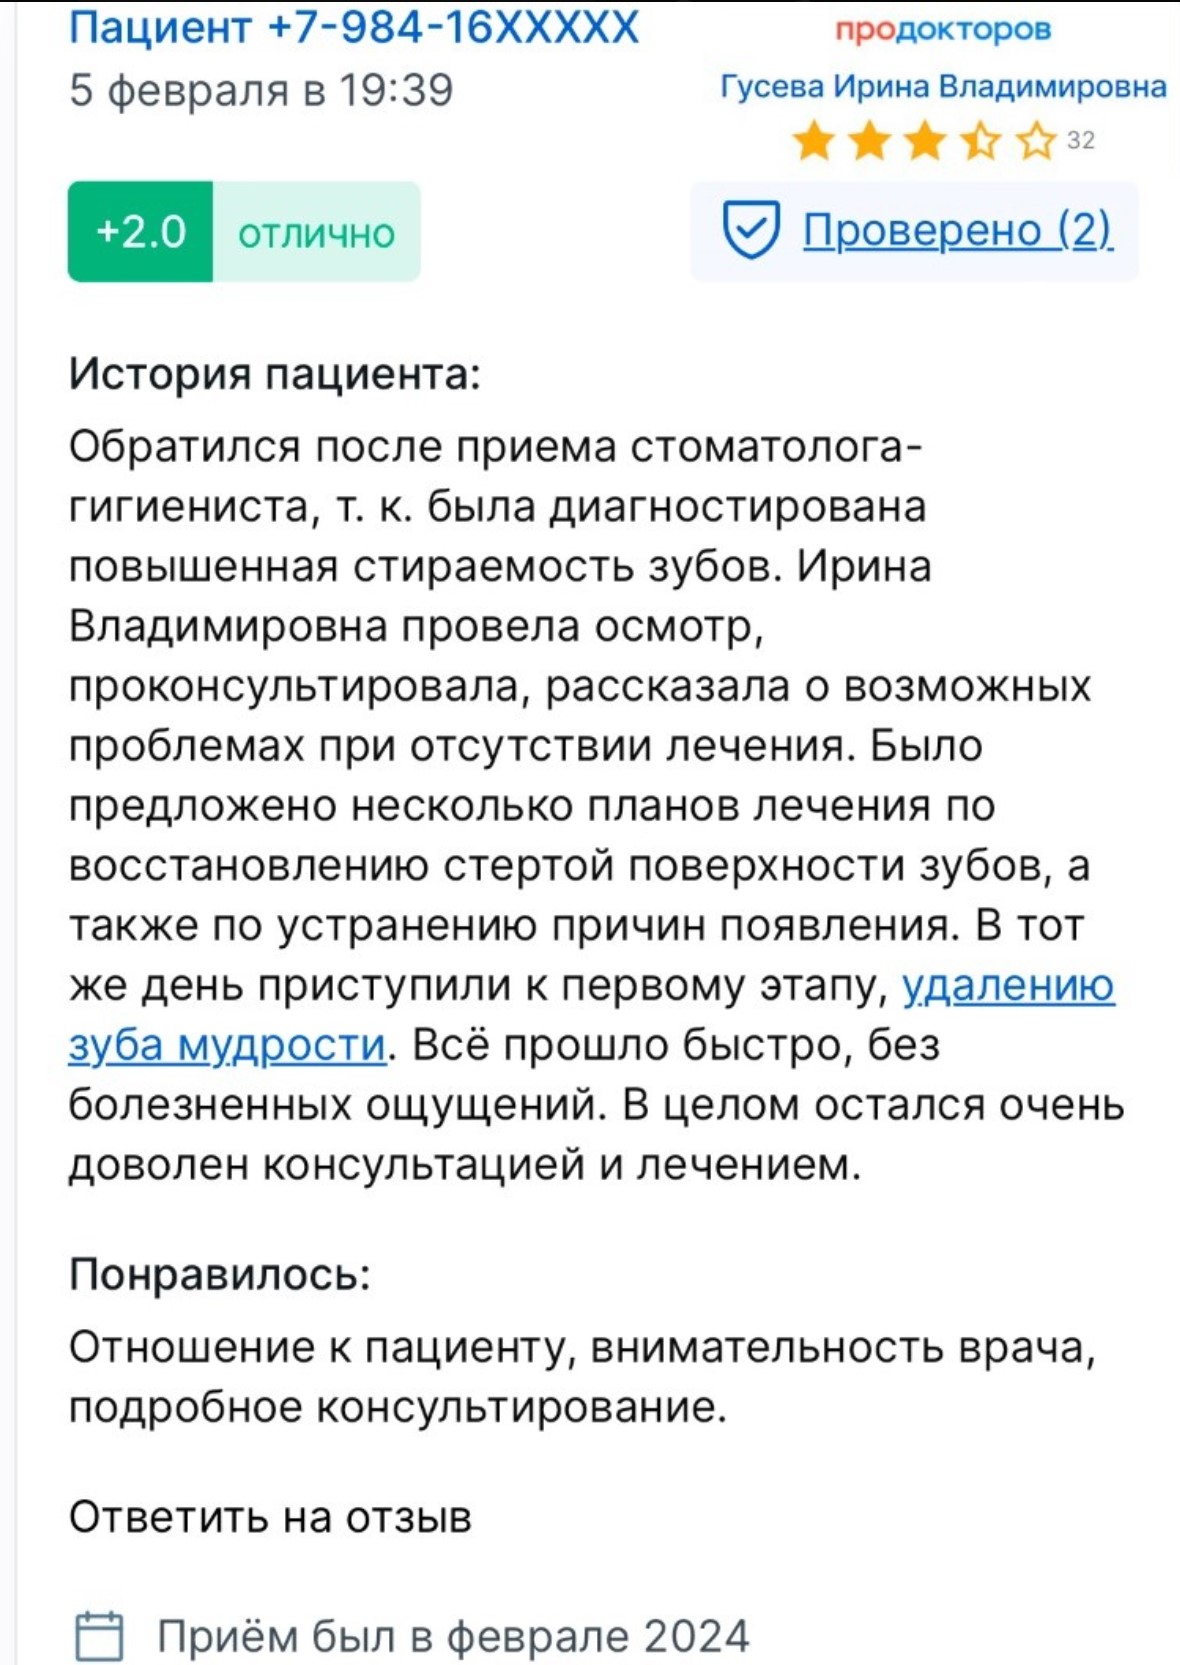

Ирина Гусевастоматолог-терапевт, имплантолог, ортопед

Ирина Гусевастоматолог-терапевт, имплантолог, ортопед